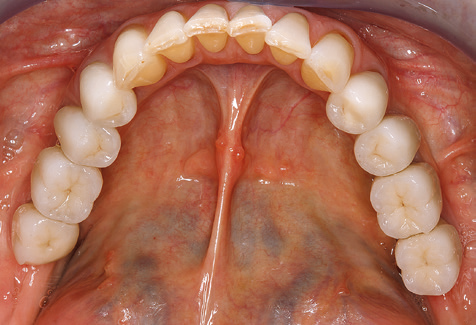

Für den klinischen Langzeiterfolg des parodontal kompromittierten Patienten ist die standardisierte und regelmäßige risikoadaptierte Betreuung im Rahmen der UPT der zentrale Baustein des Behandlungserfolgs. Dies gilt in besonderer Weise für Patienten, die nach erfolgreich abgeschlossener parodontaler Sanierung mit Implantaten versorgt wurden (Abb. 11a und b).

Aufgrund der bestehenden parodontalen Vorerkrankung erfolgte die unterstützende Parodontaltherapie (UPT) in den ersten Jahren in einem DreiMonatsIntervall. Dabei zeigte die Patientin eine hohe Motivation und gute Compliance. Bei den jährlich erhobenen Sondierungsbefunden zeigten sich stabile parodontale Verhältnisse mit einem BOPIndex unter fünf Prozent. Aufgrund der stabilen parodontalen Situation und der guten Mitarbeit der Patientin wurde ab dem sechsten Jahr der prothetischen Funktionsphase das Recallintervall auf halbjährlich umgestellt. Auch mit diesem veränderten Recallintervall zeigten sich bei der jeweils jährlichen Aufnahme des Parodontalstatus stabile parodontale Verhältnisse, ohne Zunahme der Sondierungstiefen und einem BOPIndex unter fünf Prozent (Abb. 2a und b).

Im Rahmen der ZehnJahresKontrolle zeigten sich keine Hinweise auf einen fortschreitenden parodontalen Attachmentverlust oder einen periimplantären Knochenverlust (Abb. 3).

Die Patientin befindet sich weiterhin in einem halbjährlichen Intervall für die UIT. Nachfolgend werden am Beispiel dieser Patientin die einzelnen Arbeitsschritte einer strukturierten UPTSitzung aufgezeigt, so wie sie nahezu unverändert über den gesamten Funktionszeitraum von immerhin zwölf Jahren durchgeführt wurden. Natürlich wurden über diesen Zeitraum einige neue Materialien und Geräte in das Konzept integriert. In diesem klinischen Fallbericht wird das aktuelle Material und Gerätekonzept präsentiert.